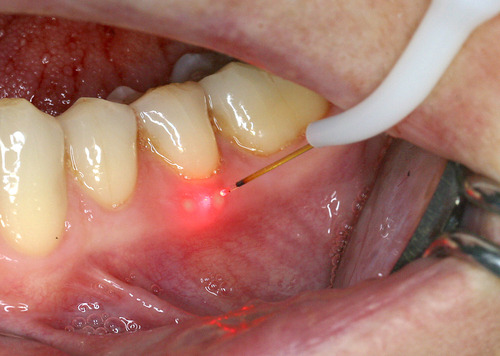

Par exemple, sur des aphtes douloureux (fig. 20) un rayonnement laser est rapproché progressivement jusqu’à une disparition quasi complète des sensibilités (fig. 21).

Fig. 21 Traitement avec un rayonnement laser pénétrant

Cette biostimulation qui peut durer plusieurs minutes aboutit en général à une guérison très rapide et indolore des ulcérations gingivales (fig. 22)